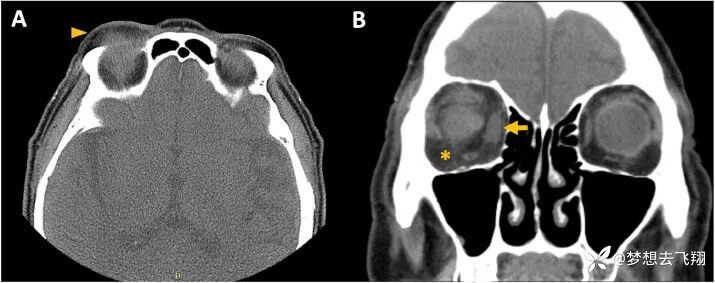

VEXAS综合征患者的眼眶CT,参考5

对上图的解释:显示轴向 (A) 和冠状 (B) 平面的眼眶计算机断层扫描 (CT),显示睑/眶周水肿(箭头)、锥内脂肪搁浅(眼眶蜂窝织炎)(星号)和内直肌扩大(眼眶肌炎)(箭头)在一名 77 岁男性 VEXAS 综合征患者右眼。